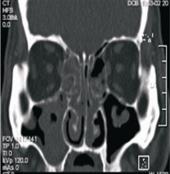

需接受手術的病患,在手術前均需接受電腦斷層掃描的詳細檢查,正常的鼻竇在影像上應為黑色的空腔(圖二),鼻竇炎手術的最新進展 「電磁式鼻竇導航手術」(相關圖片)若被發炎組織所堵塞,則呈現灰白色顯影,即為發炎感染的範圍(圖三),鼻竇炎手術的最新進展 「電磁式鼻竇導航手術」(相關圖片)也就是手術醫師要以手術器械清除的部份。一般而言,進行這樣的手術需要住院,在全身麻醉下進行,以利醫師將病灶部位徹底清除,才不會復發。